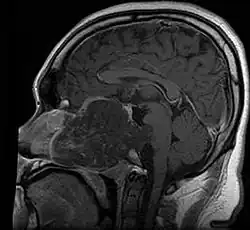

• Skull base:

• May be intracranial or extracranial, with mass effect symptoms depending on location

• Headaches and/or facial pain are common

• Pituitary insufficiency, hemianopsia/diplopia, cranial nerve deficits, nasal stuffiness.

Skull Base